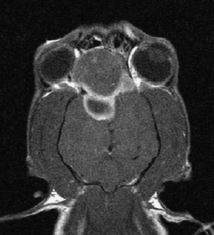

What will each stage of hemorrhage appear on T1 and T2 sequences? Article: you just need to know this :)

Hyperacute - T1 iso, T2 hyper

Acute - T1 iso, T2 hypo

Early subacute - T1 hyper, T2 hypo

Late subacute - T1 hyper, T2 hyper

Chronic - T1 hypo, T2 hypo